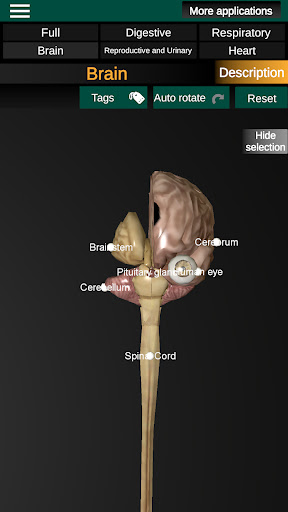

* Мозок, який включає головний мозок, мозочок і стовбур мозку.